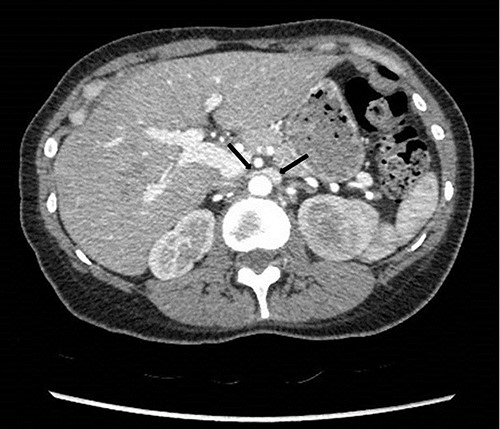

To investigate the bleeding source, she subsequently had a CT renal angiogram 3 days later that showed a narrow angle between origin of SMA and the aorta (Fig. 3) with multifocal areas of hypoattenuation throughout the left renal cortex (Fig. 4). It showed a compression ratio of 3.25 (diameter of pre-compressed vein =6.5 mm; diameter of compressed vein =2 mm) (Fig. 5).

Computed tomography angiogram on presentation showing pre-compressed LRV (right arrow); and compressed LRV (left arrow).